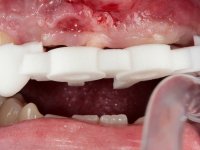

O paciente foi observado conjuntamente e a dúvida que surgiu de imediato foi se seria possível com a regeneração óssea a efectuar poder ser reabilitada naturalmente a zona das papilas interdentárias. Nesse sentido foi feito um enceramento de diagnóstico que contemplaria as duas hipóteses, utilizando ou não a cerâmica gengival. A confecção desse enceramento foi fundamental para expor ao paciente a dificuldade da reabilitação. O wax-up deu origem a um mock-up que foi aprovado pelo paciente e que simultaneamente serviu de guia imagiológica. O caso foi planificado cirurgicamente e realizada uma guia cirúrgica com que foram colocados os implantes. Após 10 semanas foi feita a 1ª impressão para confecção da ponte provisória. Foram criados os primeiros perfis de emergência na gengiva artificial e foi digitalizado o modelo. Por processo de CAD-CAM foi confeccionada uma ponte provisória aparafusada baseada no enceramento de diagnóstico. A ponte trabalhou durante 8 semanas os tecidos moles que foram fielmente copiados numa impressão com técnica de moldeira aberta. Os transferes foram individualizados com resina composta para copiarem fielmente os perfis de emergência criados pela ponte provisória. Confeccionado o modelo de trabalho definitivo, foi realizada uma infra-estrutura em zircónio seguindo a orientação do enceramento de diagnóstico. O assentamento da infra-estrutura foi testado em boca e simultaneamente foi novamente impressionados os tecidos moles com um silicone fluido. Nessa consulta foi feito o levantamento da cor. Os dentes 13 e 23 apresentavam uma saturação anormalmente forte que resolvemos não valorizar, optando por privilegiar a relação com o sector antero-inferior. Foi realizada uma nova gengiva artificial com a impressão que acompanhou a impressão de arrasto com a infra-estrutura. Após a colocação da cerâmica na infra-estrutura foram coladas as meso-estruturas. O trabalho final foi aparafusado lentamente permitindo a adaptação dos tecidos moles.